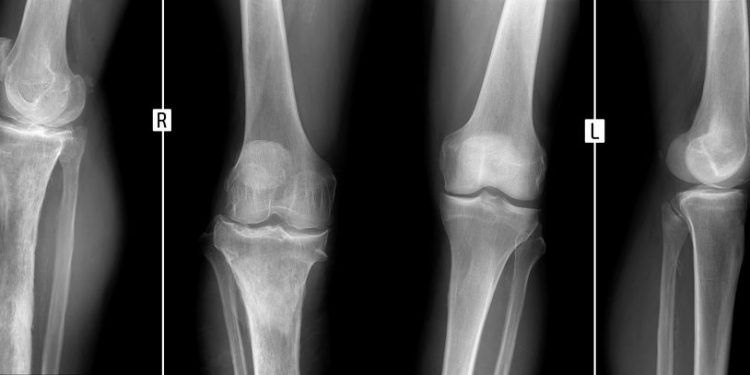

Sometimes the doctor may order tests to look at your bone or the area around it, such as an x-ray and an MRI scan. A bone MRI can show the structure of your bones and can help identify nearby infections like abscesses.